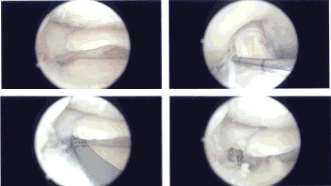

Examination of the medial tibiofemoral compartment showed a tear of the medial meniscus root. A medial entry portal was made with the use of a spinal needle. Debridement of the meniscus root was confirmed and a side port insertion of the meniscus root was planned.

There was grade 1 to grade 2 osteoarthritic changes in the medial femoral condyle for which chondroplasty was performed. Examination of the intercondylar notch showed intact ACL. Examination of the lateral tibiofemoral compartment showed intact meniscus and cartilage.

Examination of the patellofemoral compartment showed grade 1 to grade 2 osteoarthritic changes, which were obtained with shaver. The planning for a medial meniscus root repair was done.

A meniscus root repair jig was inserted through the medial portal and placed at 7.5 mm anterior to the posterior mark. Flip cutter was inserted through a separate incision over the medial tibia guided by the jig. Once it was out, it was flipped and about a 5-mm tunnel was made.

Curette was further used to decorticate the bone inside the knee also. Scorpion was used to pass 2 FiberTak’s through the root, one deep and one superficial. The sutures were passed through the interosseous tunnel with the use of suture passer.

Once they were there, then the root was very well induced. The sutures were put into the tibia with the use of 4.75-mm SwiveLock and good tension was achieved, which was checked intraoperatively, and the pictures were taken and saved.

Microfracture chondroplasty was done with the use of a chondroplasty pick from Arthrex with the use of the shaver handle and 4 holes were made. The water was cut to see that there was good flow of blood from those holes.

Intraoperative Arthroscopy Images